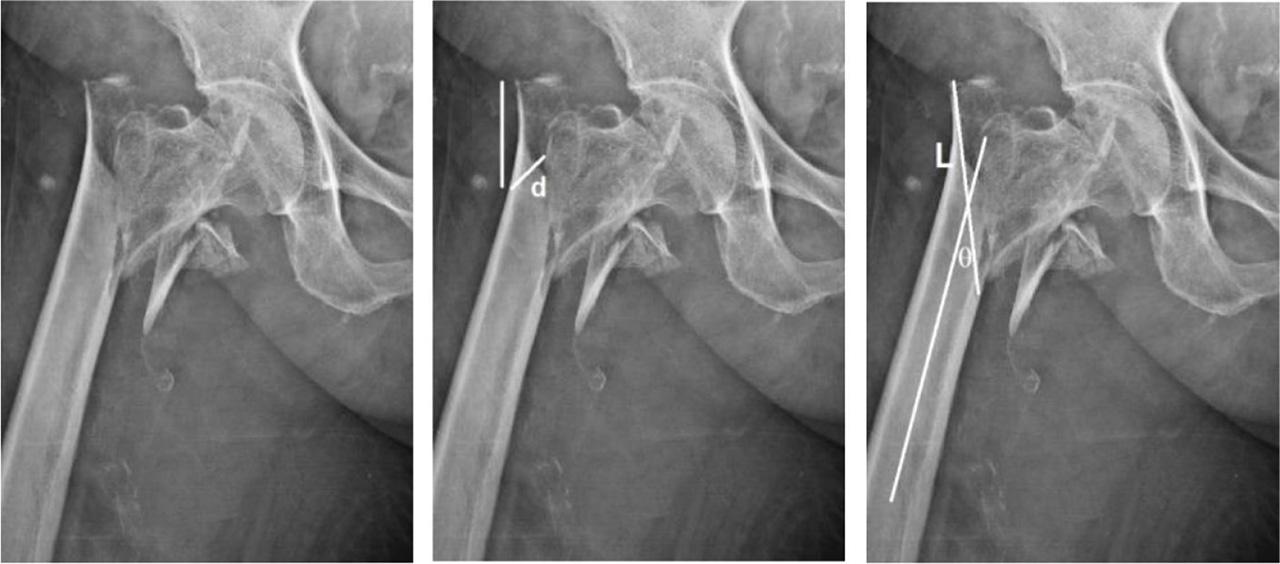

Figure 2.